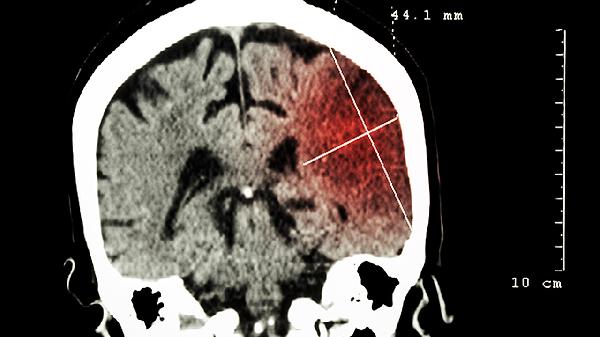

高热期间建议保持每日2000毫升以上饮水量,选择电解质饮料或淡盐水。采用温水擦浴等物理降温时避免酒精擦拭。体温超过38.5度可考虑使用对乙酰氨基酚等退热药物,但需遵医嘱控制用药间隔。恢复期保证优质蛋白和维生素B族摄入,如鸡蛋、深海鱼、全谷物等,避免剧烈用脑。若出现嗜睡、抽搐或认知功能异常,需立即进行头颅CT或腰穿检查。